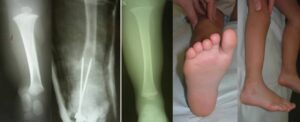

In fibular hemimelia, it is preferable to correct the foot and ankle deformity early (18-24 months of age)

and maintain it as the child grows, rather than having them walk with their foot in the deformed position. Various procedures have been described for this purpose, depending on the type of deformity present. The various alterations present (residual fibular joint, ankle valgus, subtalar fusion, peroneal and Achilles tendon contracture, etc.) are corrected to ensure good foot support.

The combination of all these procedures, in the most severe cases of fibular hemimelia , is called the SUPER-Ankle procedure (Paley D, J Child Orthop 2016: Surgical reconstruction for fibular hemimelia)